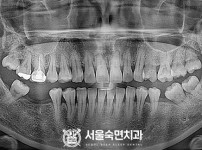

임플란트-전후사진1

임플란트-전후사진2

임플란트-전후사진3

임플란트-전후사진4

치과를-선택할-때-꼭-확인하세요-서울숙면치과-임플란트-전후사진